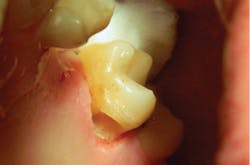

With the help of magnification, we are able to prepare small Class II lesions without sacrificing the marginal ridge, ensuring the longevity of our restoration and maximizing the remaining tooth structure with this minimally invasive approach (figures 3a–3d).

Figures 3a–3d: Minimally invasive Class II preparation with marginal ridge preservation